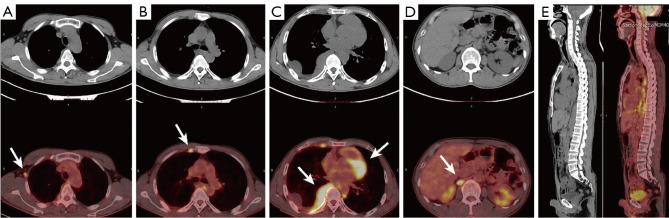

We report the case of a 54-year-old Chinese man with no notable medical history who complained of cough, sputum, and shortness of breath for 3 months. He had a positive purified protein derivative (PPD) test. An initial misdiagnosis of pleural tuberculosis was corrected, after 3 thoracoscopic biopsies and tests, to primary pleural MALT lymphoma. He received treatments of R-CHOP (rituximab, cyclophosphamide, epirubicin, vindesine and prednisolone) and traditional Chinese medicine. The patient was followed for 3 years until June 2022, with no obvious respiratory symptoms. Pleural MALT lymphoma is extremely rare, with only a few cases reported. This article describes our case, and includes an overview of 15 previously reported cases to summarize the characteristics, treatments, and prognosis of primary pleural MALT lymphoma.

Pleural MALT lymphoma is rare, and a correct diagnosis depends on tissue biopsy, immunohistochemical staining, and detection of gene rearrangement. Thoracoscopy is important to diagnose this disease. Multiple thoracoscopic biopsies may be necessary.